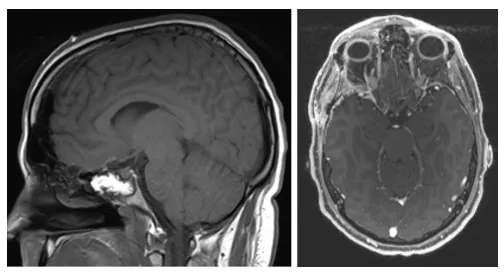

最终患者接受经额颞颞入路肿瘤切除术。术中见肿瘤质地柔软,已压迫右侧视神经。手术实现肿瘤全切(图3),视神经管获得充分减压。术后病理确诊为WHO Ⅱ级脑膜瘤。

图3.(左)矢状位T1加权及(右)轴位T1加权增强MRI显示病变全切除,未见残留病灶。

术后患者头痛显著改善,右眼视力问题消失。术后3个月接受辅助放疗(总剂量5400 cGy/30次),虽出现皮肤反应及疲劳症状,但末次随访(术后5个月)时神经功能完好,未遗留任何后遗症。